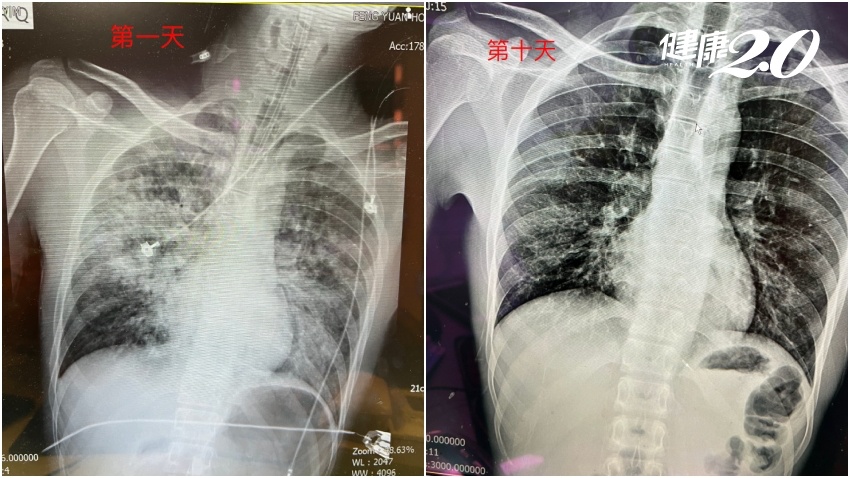

林口長庚醫療團隊由整外專家陳建宗院長領軍

院方和林志穎家屬皆不透露林志穎病情,但自事發當天,已經由院長陳建宗領軍組成醫療團隊,由於陳建宗是顏面整形專家,顏面骨重建的部分就是由陳建宗負責,另外還有骨科、神經外科及一般外科負責頭部外傷的照護和外傷照護。

網路上有人討論林志穎顏面傷嚴重,擔心顏面重建恐要花很長的時間。但其實長久以來長庚醫院的整形重建技術在國內醫界就是數一數二的地位,顱顏重建更是國際知名,有專家照護之下,粉絲們想要看到林志穎恢復偶像帥臉不是問題。